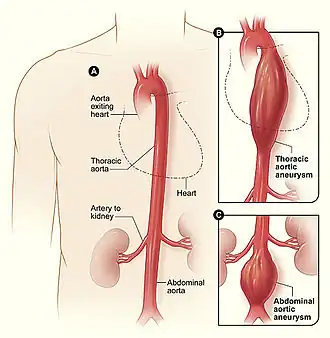

Anévrisme de l'aorte

Il s'agit d'une dilatation du calibre de l'artère. Il peut intéresser tout segment de l'aorte. La localisation la plus fréquente se situe en dessous des artères rénales, c'est-à-dire dans la dernière portion de l'aorte. On parle alors d'anévrisme de l'aorte abdominale. Une autre localisation est l'anévrisme de l'aorte ascendante, située au niveau du thorax et comportant certaines spécificités.